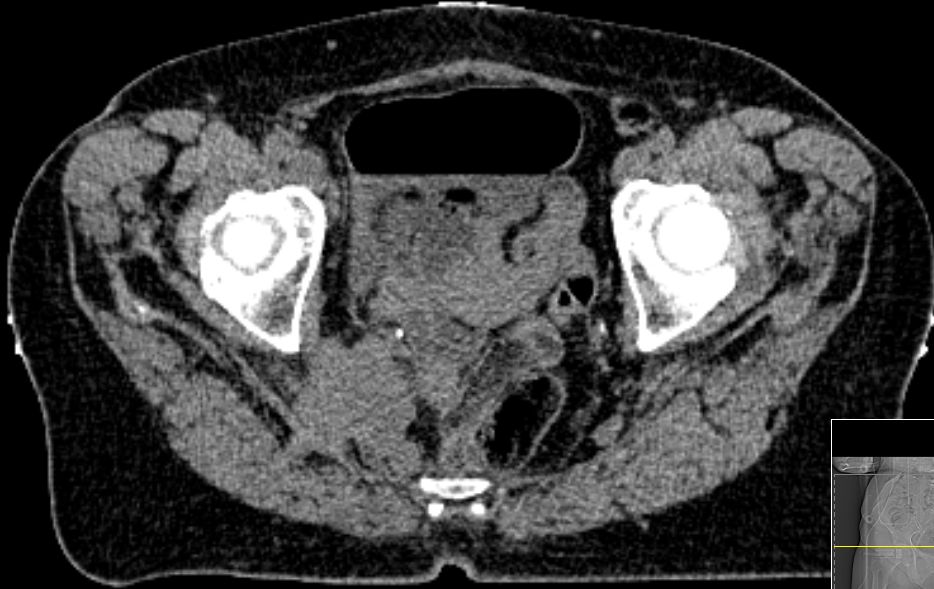

64jährige Frau, die 1 Jahr nach Melanommetastasen der linken Leiste

einen vergrößerten Lymphknoten lateral der A. iliaca externa links entwickelte.